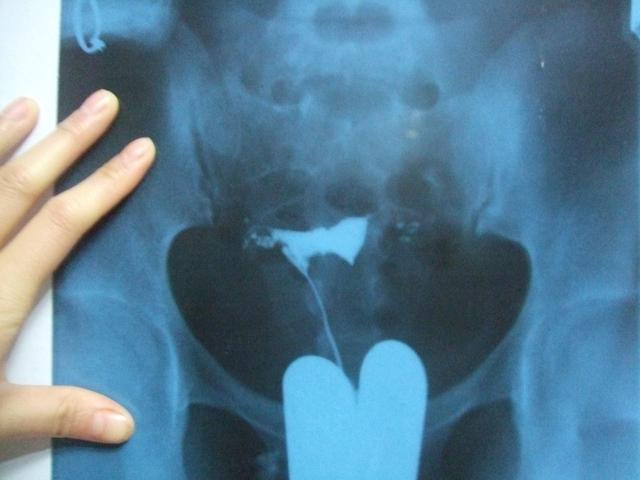

但是随着年龄的增长,她和老公都开始不淡定了,于是开始走上了到各大医院求子的道路。也是在这个过程中,小凤发现自己患有多囊。再过了半年,医生让小凤回去当地促排,试试看能不能怀孕。但是当地的医院却说,像小凤这种情况,最好是做个造影,看看输卵管通不通。小凤听说,假如说做造影的时候不痛,说明就是通的。否则就是不通。在造影的过程中,小凤真心觉得自己一点都不痛,她的内心非常高兴,觉得应该是没问题的。

但是,造影的结果却显示她两个输卵管一侧不通,另一侧是通而不畅,也就是说都有问题,这对小凤来说又是一个沉重的打击。接着,医生按照常规的做法提出让小凤做腹腔镜手术。小凤在网上查了又查,还是不放心。她看到很多人都是做了腹腔镜手术之后也没有怀孕,而且手术费用也要1万多。小凤觉得与其花一万多去做这样一个不知道效果如何的手术,还不如做试管。对于小凤的这种想法,小编是非常支持的,小编也觉得何必用1万多钱去博一个未可知的将来呢?很多人在做了腹腔镜手术之后每怀孕最终还是做了试管,于是走这么多弯路去尝试,还真的不如一步到位。